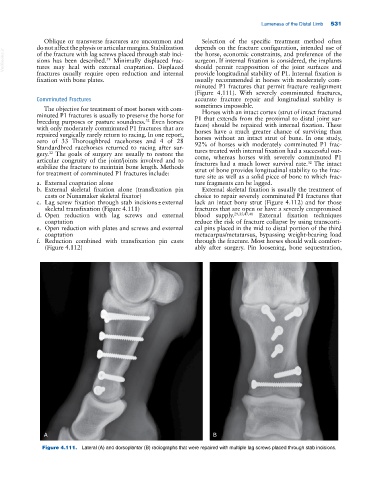

c. Lag screw fixation through stab incisions ± external lack an intact bony strut (Figure 4.112) and for those

skeletal transfixation (Figure 4.111) fractures that are open or have a severely compromised

Figure 4.111. Lateral (A) and dorsoplantar (B) radiographs that were repaired with multiple lag screws placed through stab incisions.